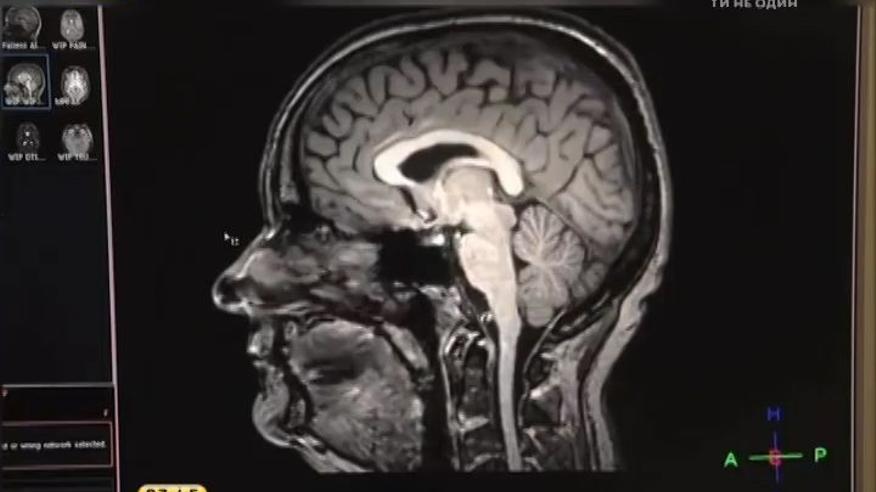

Що відбувається зі стресом в організмі – чи може він накопичуватися та, які проблеми зі здоров’ям спровокувати?